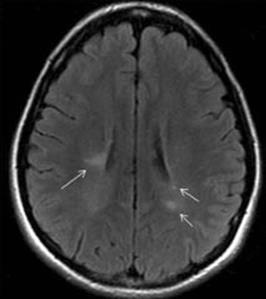

Figure 22.1 Axial FLAIR MRI showing characteristic T2-hyperintense plaques (arrows) in a patient with MS.

T2 and fluid attenuation inversion recovery imaging

The T2 hyperintense plaque is the characteristic MRI finding of demyelination secondary to MS (Figure 22.1). Plaques are generally easier to visualize by FLAIR, a sequence in which the bright CSF signal is removed. Common plaque locations are in the periventricular white matter, corpus callosum, centrum semiovale, and middle cerebellar peduncle. Although plaques may have a variety of appearances, those that are ovoid in shape are most suggestive of MS. Lesions in the corpus callosum that are oriented perpendicularly to the lateral ventricles are known as Dawson’s fingers (Figure 22.2) and are particularly characteristic of MS. These lesions are best visualized using FLAIR sequences in the sagittal plane. Plaques may accompany both new and old (presumably inactive) MS symptoms.